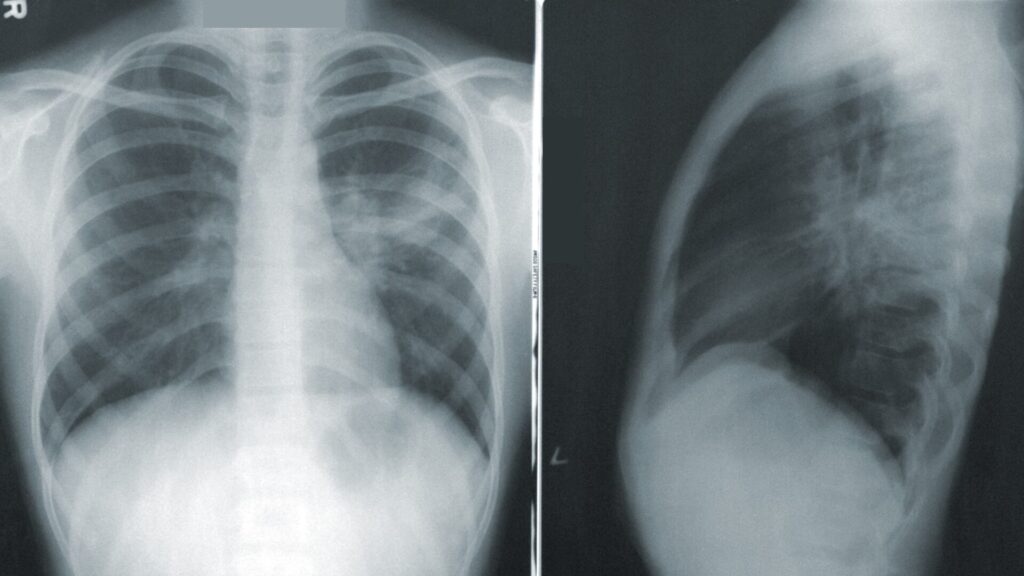

Predicting Survival: Chest X-Rays Provide Vital Insight for Hospitalized COVID-19 Patients